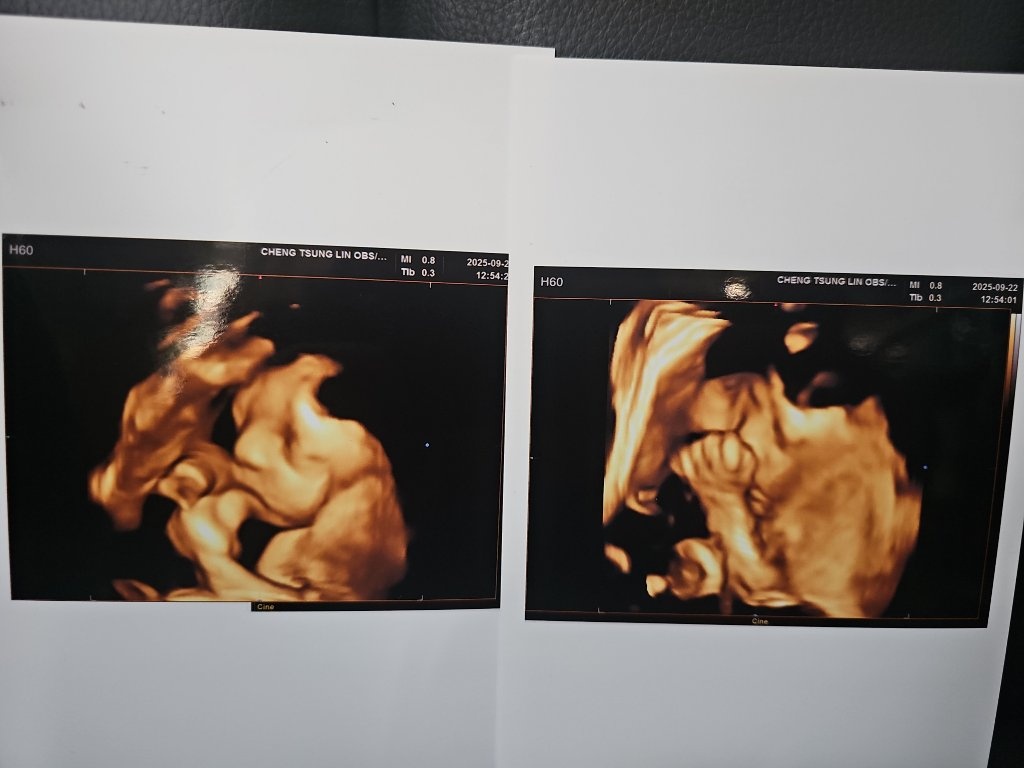

昨天來去產檢,魚卵仔在睡覺,拍出來的照片又是遮臉,醫生搖了好久才讓他把手放下來(改成放在嘴邊繼續睡)

https://images.plurk.com/705CU3ddvax9HRKeclEFFV.jpg ~欣迪~ : 每次拍照都愛遮臉

~欣迪~ : 每次拍照都一臉嚴肅